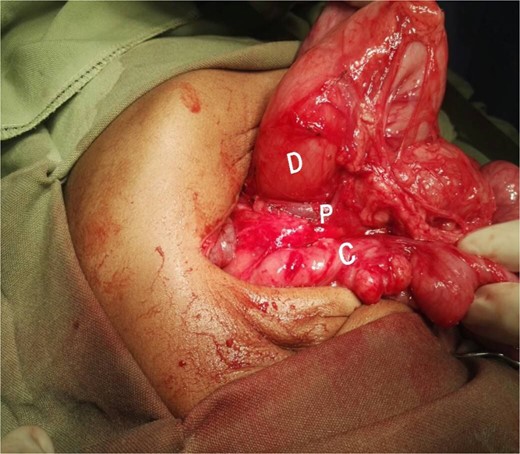

A 21-month-old girl presented with a history of bilious emesis since birth. The mother reported that the infant had several occasions of bilious emesis to a local doctor where she was managed as a case of dehydration. At 14 months of age, she was referred to a tertiary hospital for failure to thrive, where she was diagnosed with malrotation and underwent a Ladd’s procedure. However, the bilious vomiting continued. Upon arrival at our hospital, she was severely emaciated, dehydrated, and pale. Abdominal examination revealed visible epigastric peristalsis and right upper transverse surgical scar. After rehydration and correction of electrolyte imbalances, an upper gastrointestinal series showed signs of partial duodenal obstruction (Fig. 1). Abdominal exploration through the previous incision was done with findings of multiple adhesions that were gently released. The cecum was found in the left iliac fossa, and the appendix was not found. Potential causes of CDO such as malrotation, annular pancreas, and intestinal duplication were ruled out, following the duodenum, a PDPV was found causing the obstruction (Fig. 2). A diamond-shaped duodenoduodenostomy was performed, leaving the PDPV tunneled behind the anastomosis. The patient had a smooth post-operative recovery, gaining 1.7 kg in three weeks. Six months later, she was thriving, with her weight in the 90th percentile for her age.

Intraoperative picture showing the PDPV crossing over the duodenum and causing duodenal obstruction. C, colon; D, duodenum; P, preduodenal portal vein.